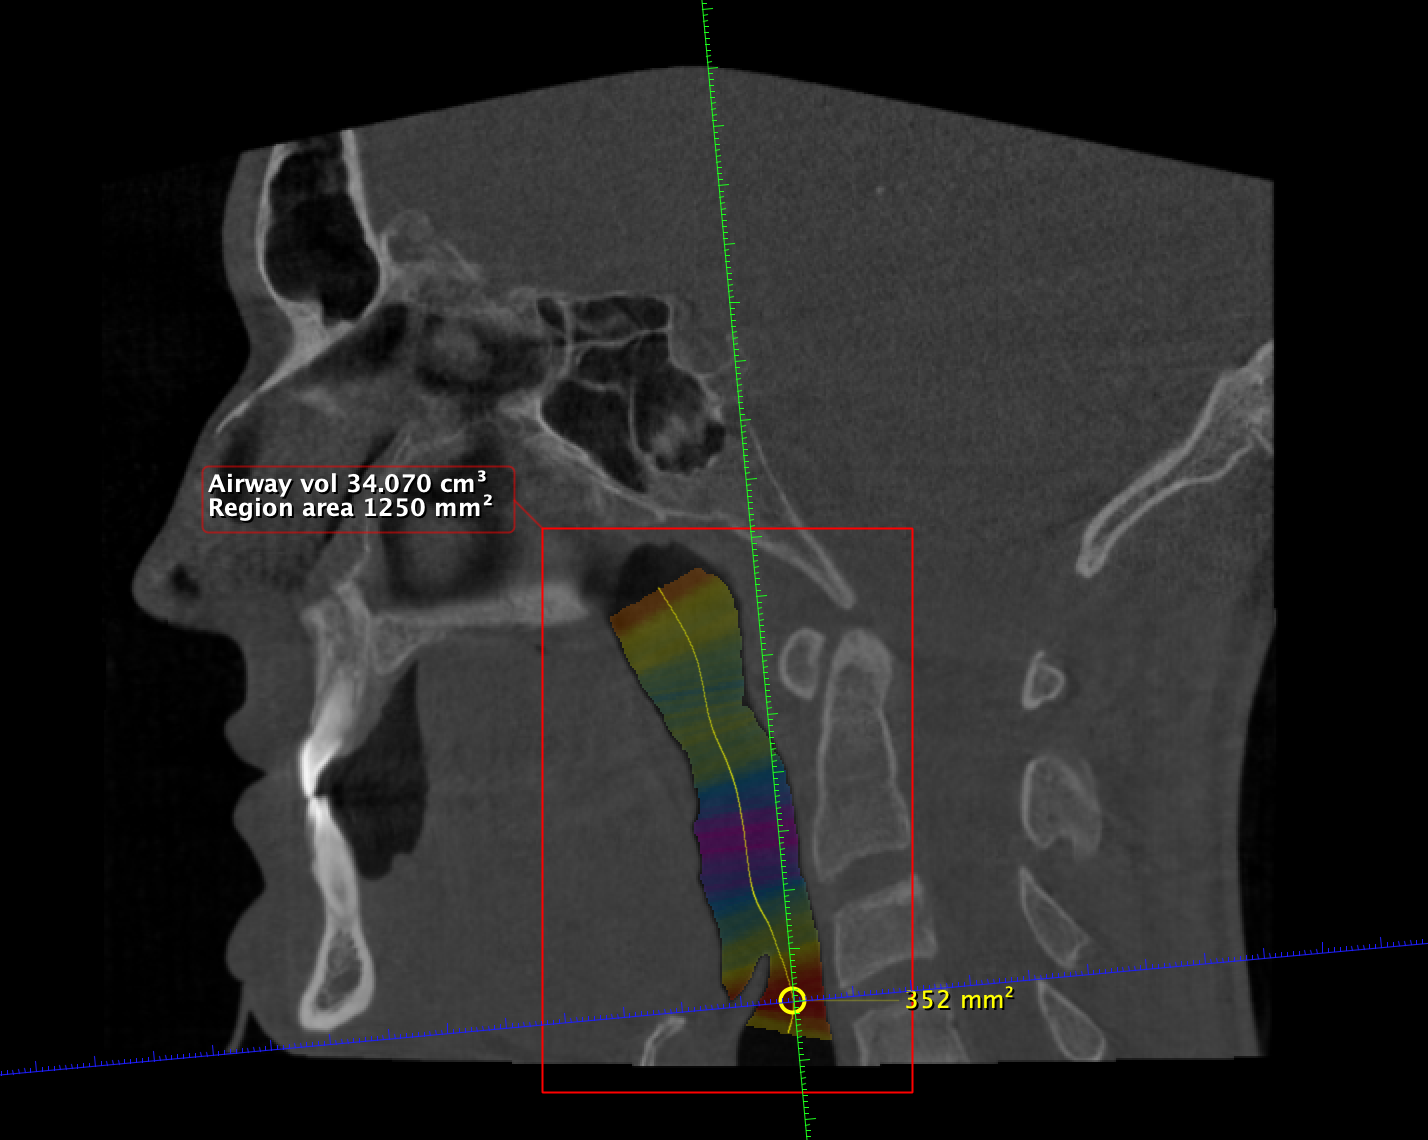

Double Jaw Surgery + Genioplasty

At least 4* of counter clockwise rotation on both jaws.

5mm+ advancement on both maxilla and mandible

7mm+ genioplasty

My jaw surgery movements are limited because of my natural unfortunate teeth position and a combination of other factors.

Double Jaw Surgery + Genioplasty

At least 4* of counter clockwise rotation on both jaws.

5mm+ advancement on both maxilla and mandible

7mm+ genioplasty

My jaw surgery movements are limited because of my natural unfortunate teeth position and a combination of other factors.